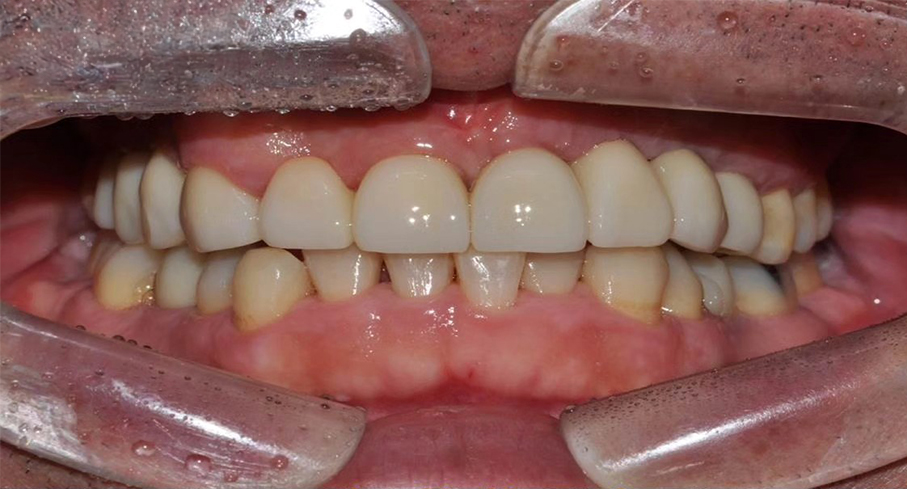

치유가 완료되면, 정밀한 디지털 스캐닝을 통해 자연스럽고 편안한 보철물을 제작합니다. 자체 기공실에서 맞춤 제작된 보철물은 정밀한 맞춤 제작으로 자연스러운 심미성을 추구합니다. 이후 심어놓은 임플란트 위에 치아 보철물을 위한 기둥을 세우고, 이 기둥을 이용하여 보철물을 장착합니다.